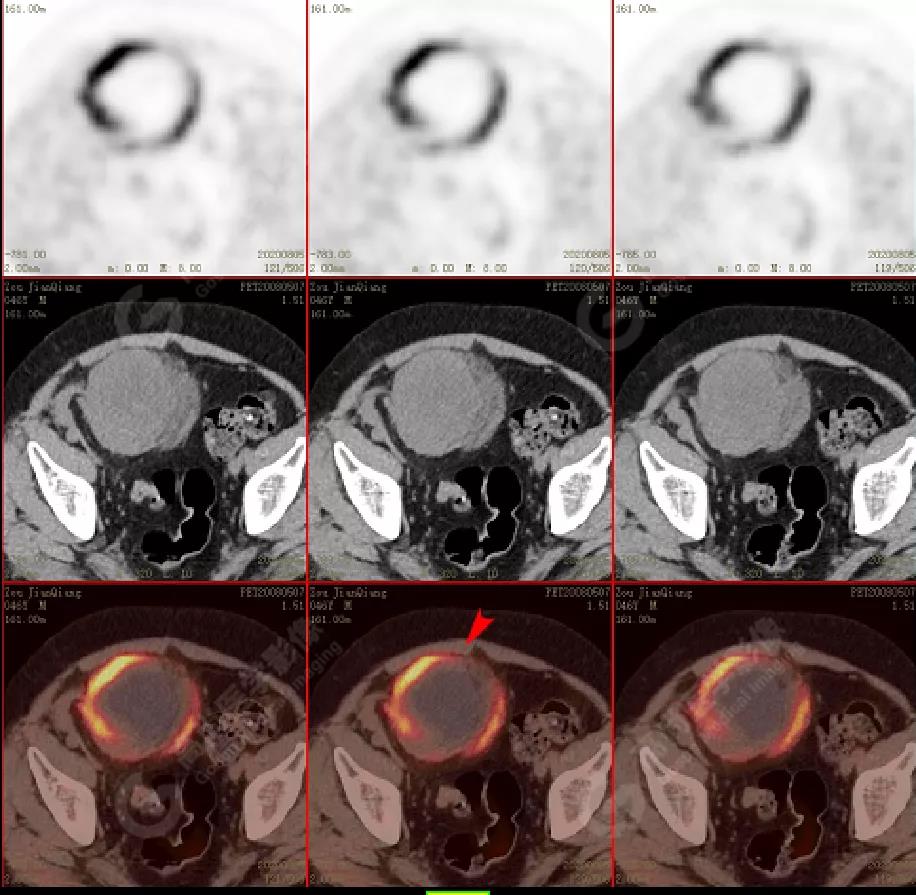

↑移植腎下部等密度腫塊,代謝環(huán)狀增高,SUVmax13.4,中心代謝缺損